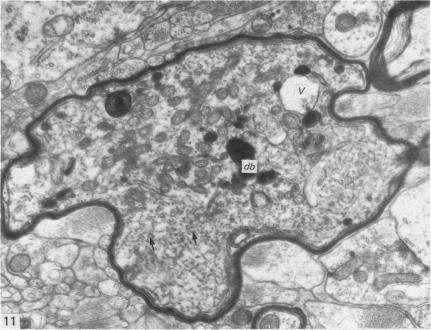

The ultrastructural changes following a single intracisternal injection of 6-OHDA were studied in the intermediolateral nucleus of the monkey spinal cord. Post-operative survival periods ranged from 20 hours to 14 days. At all stages, only boutons containing clear, round vesicles (R-boutons) and those containing dense-cored vesicles (DCV-boutons) underwent degeneration. Boutons containing flattened vesicles (F-boutons) appeared to be unaffected. Changes were seen even at 20 hours after injection and these were confined to R-boutons only. The changes included an initial swelling and crowding of the vesicles, followed by an increase in the electron density of the axoplasm. The latter change was most marked on the second post-operative day and by the third day, most of the electron-dense profiles were glia-engulfed. By the third day, also, many unmyelinated and, occasionally, myelinated axons showed accumulations of mitochondria, membrane-bound tubular profiles and electron-dense bodies. Many astrocytic processes also showed accumulation of tubular profiles. From the fifth day onwards, few degenerating R-boutons were encountered but DCV-boutons containing swollen vesicles, with or without their dense cores, were obvious. Unmyelinated and, occasionally, myelinated axons and astrocytic processes containing tubular elements still continued to be seen. By the fourteenth post-operative day, degenerating profiles were rarely observed. The probable significance of these findings has been discussed in the light of recent anatomical and biochemical studies.

在猴脊髓中间外侧核中,研究了单次脑池内注射6-羟基多巴胺(6-OHDA)后的超微结构变化。术后存活期从20小时至14天不等。在所有阶段,只有含有清亮圆形囊泡的终扣(R终扣)和含有致密核心囊泡的终扣(DCV终扣)发生退变。含有扁平囊泡的终扣(F终扣)似乎未受影响。甚至在注射后20小时就可见到变化,且这些变化仅局限于R终扣。变化包括囊泡最初肿胀和聚集,随后轴浆电子密度增加。后者的变化在术后第二天最为明显,到第三天,大多数电子致密图像被胶质细胞吞噬。同样在第三天,许多无髓鞘以及偶尔有髓鞘的轴突显示出线粒体、膜结合管状结构和电子致密体的聚集。许多星形胶质细胞突起也显示出管状结构的聚集。从第五天起,很少遇到退变的R终扣,但含有肿胀囊泡(有或无致密核心)的DCV终扣很明显。仍可继续见到含有管状成分的无髓鞘以及偶尔有髓鞘的轴突和星形胶质细胞突起。到术后第十四天,很少观察到退变图像。已根据最近的解剖学和生物化学研究对这些发现的可能意义进行了讨论。